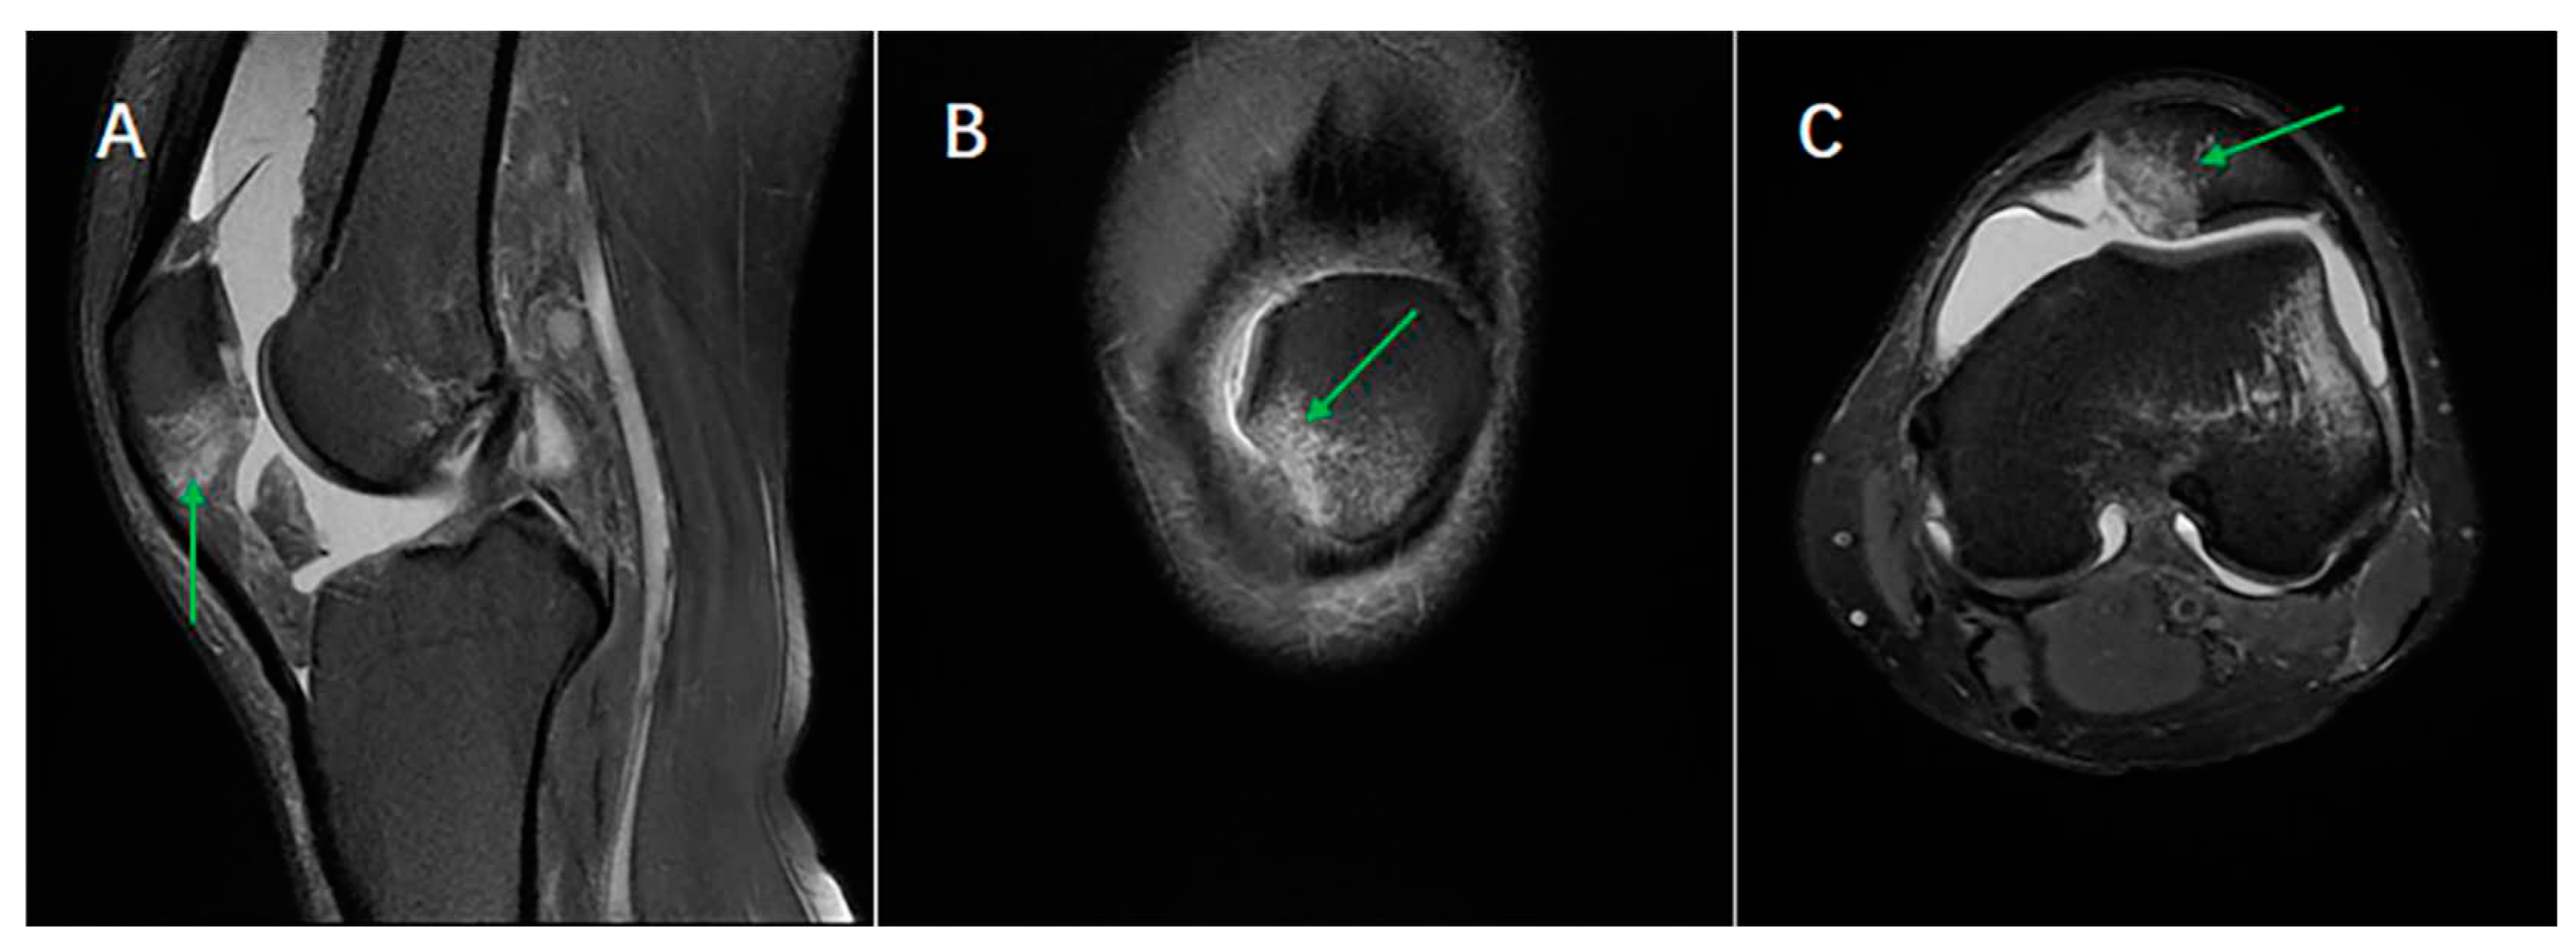

Figure 1. Method of calculating the bone bruise location to classify the bone bruise pattern of ACL in sagittal plane.

The bone bruise location in the lateral-medial and superior-inferior directions was first determined using a sagittal and transverse plane imaging sequence. (Figure 1 and Figure 2). The precise locations in the lateral-medial direction were confirmed using the following formula:

ML   =     M m a x / M t o t a l 100 % 36

Mmax is defined as the number of slices at which the gray value is maximum among all the slices in the order of lateral-medial sides in the sagittal plane, whereas Mtotal is the total number of slices in the sagittal plane based on the presence of bone segments. ML is a measure of the location in the lateral-medial direction, and it ranges from 0% (closer to the lateral side of the femoral trochlea or patellar) to 100% (closer to the medial side of the femoral trochlea or patellar).

The method of precise bone bruise location in the superior-inferior direction was similar to the lateral-medial sides of the bone, which was determined using the following formula:

SI   =   N m a x / N t o t a l 100 %

Nmax is defined as the number of slices at which the gray value is maximum among all the slices in the order of superior-inferior sides in the transverse plane, whereas Ntotal is the total number of slices in the transverse plane based on the presence of bone segments. SI is a measure of the location in the superior-inferior direction, and it ranges from 0% (closer to the superior side of the femoral trochlea or patellar) to 100% (closer to the inferior side of the femoral trochlea or patellar). Selecting the image of the largest anterior and posterior diameter of the femoral condyle as the reference, bone bruise in femur most superior ends was defined as the location where three slices (10.5mm) from horizontal tangent of femoral posterior condyle cartilage margin, and bone bruise in femur most inferior ends was defined as where horizontal tangent parallel to the bottom of femoral condyle in sagittal plane.